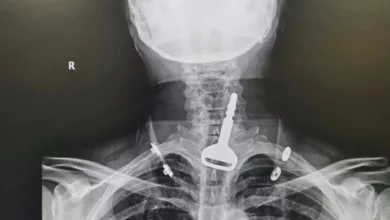

سعودي يبتلع مفتاح سيارته

في حادثة غريبة.. سعودي يبتلع مفتاح سيارته

تمكن فريق طبي بمدينة القنفذة السعودية من استخراج مفتاح سيارة عالق بالجهاز التنفسي لمريض أربعيني، في عملية استغرقت 15 دقيقة عن طريق المنظار، وأسفرت عن